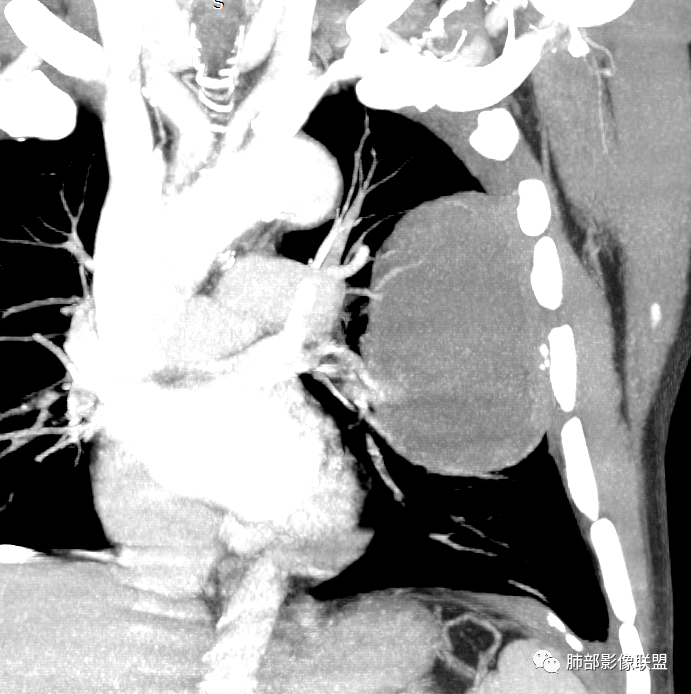

我再建一下血管。支气管进入,但是近端推移,堵塞

大肿块,边缘光滑,深分叶

近端支气管堵塞、推移为主

部分类似于脐凹征

内部支气管扩张

肺动脉推移为主,边缘部分进入

大肿块、表面光滑但深分叶,肺门侧支气管堵塞

回头看,内部支气管近端其实不连续,伴随肺动脉不存在

这两点就不符合

5)肿瘤强化方式:肺部恶性肿瘤强化程度与其血供丰富程度相关,血供丰富多强化明显,反之则较差。由于PSC 周边实性部分富血供及内部黏液变性、坏死,增强后肿块多数呈轻-中度边缘环形强化或不均匀小斑片状强化。国外学者对照病理发现肿瘤细胞或胶原组织增强扫描时强化,无强化的低密度区代表了黏液样变性区和出血坏死区。